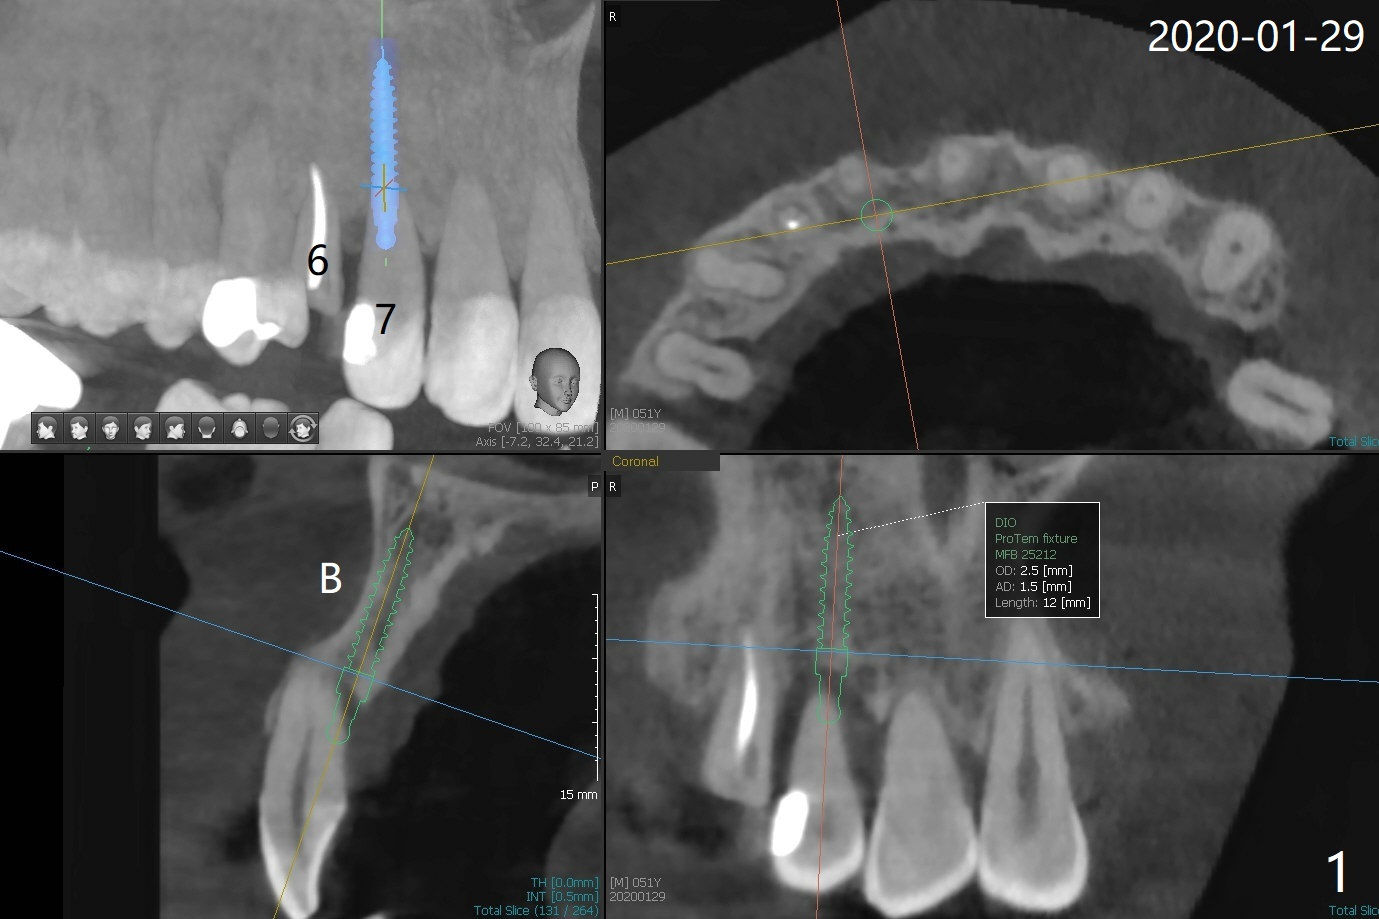

Lateral Implant/Canine Post

The tooth #7 (52 y/o, M, smoker) has mobility 2 months post #24/26, 30 implant placement without provisional (Fig.1,2) and seems to be necessary to be extracted for implant, while post and crown will be placed at #6 (Fig.3).